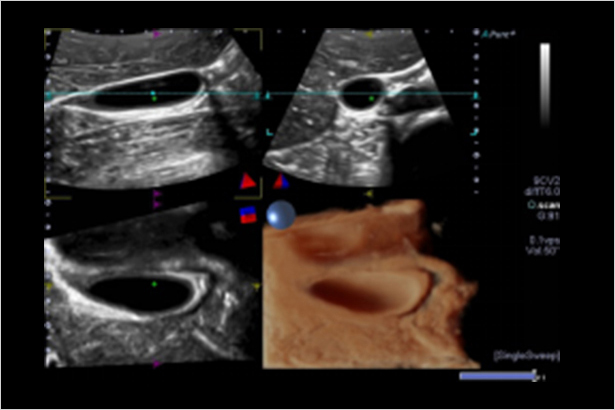

讓皮膚看起來平滑、自然,讓圖像具有逼真的效果。它自由移動的光源讓深度和細節具有強烈沖擊力。改変光源位置能幫助您準確、清楚地確定病理改變和皮膚缺陷